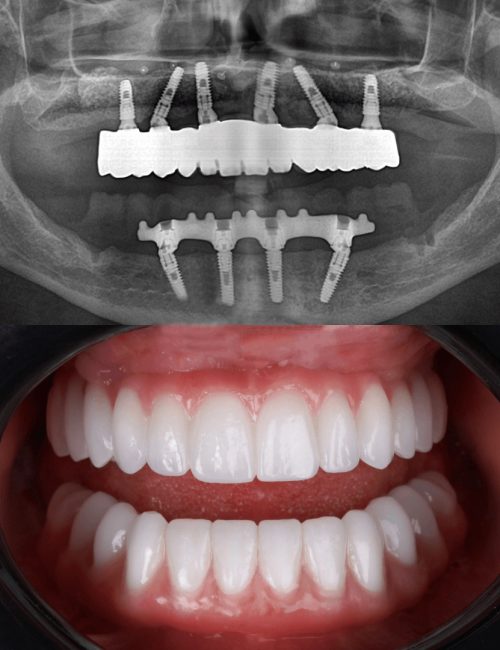

Caratteristiche dell’implantologia All on 4

Protesi fissa su 4 impianti comprende una intera arcata dentale con una flangia di gengiva (overdentura), ed è una delle alternative più veloci ed economiche per avere di nuovo denti fissi anzichè una dentiera mobile.

Caratteristiche dell’implantologia All on 6

Protesi fissa su 6 impianti consiste nell’applicazione di una protesi di 12-14 denti, sorretta da 6 impianti. All on 6 è la tecnica piu innovativa dell’implantologia per ricostruire un’intera arcata con dei denti fissi.